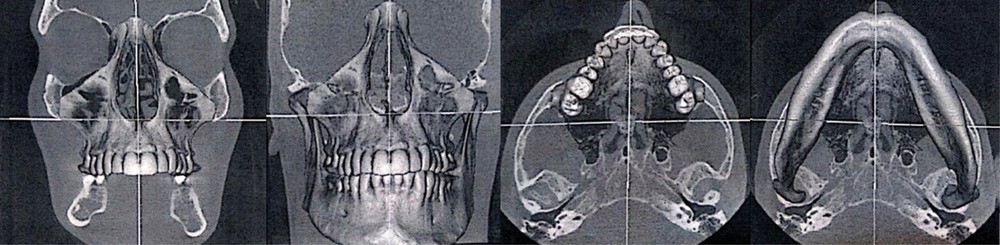

► Les examens radiographiques 3D à type de CBCT permettent de mettre en évidence un condyle gauche plus volumineux que le condyle droit, et un bord basilaire gauche plus bas que le droit (fig. 3 et 4), provoquant une asymétrie dans le sens frontal, avec une mandibule abaissée vers le bas et vers l’avant. Le diagnostic d’une hypercondylie mandibulaire est évoqué avec le patient.